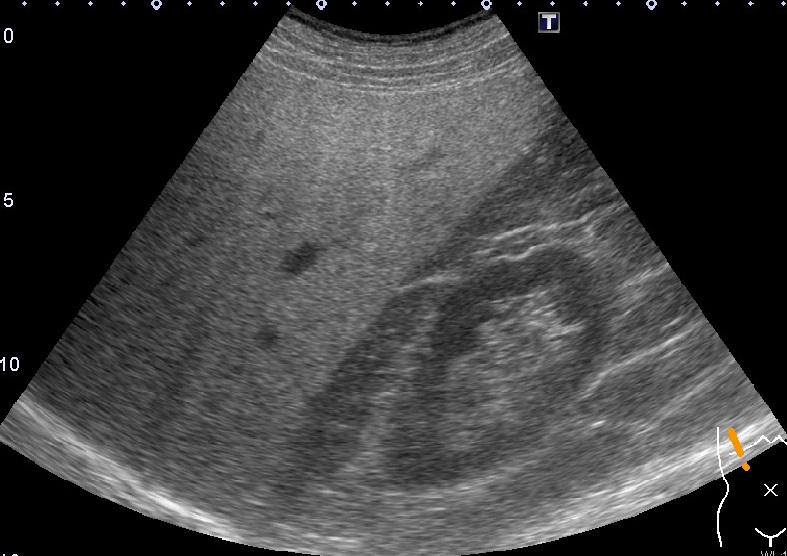

超音波検査室

超音波検査では通常の腹部検査に加えFibroScanによる肝硬度が評価可能です。FibroScanはプローブからせん断波を発振し伝搬する速度を計測します。せん断波は肝臓が硬ければ早く伝搬し軟らかければゆっくりと伝搬する性質があります。また同時に肝臓の脂肪量も評価でき肝硬変だけでなく脂肪肝や非アルコール性脂肪肝炎(NASH)などの診断にも有用です。

上腹部超音波+肝硬度測定

非アルコール性脂肪肝炎(NASH)症例